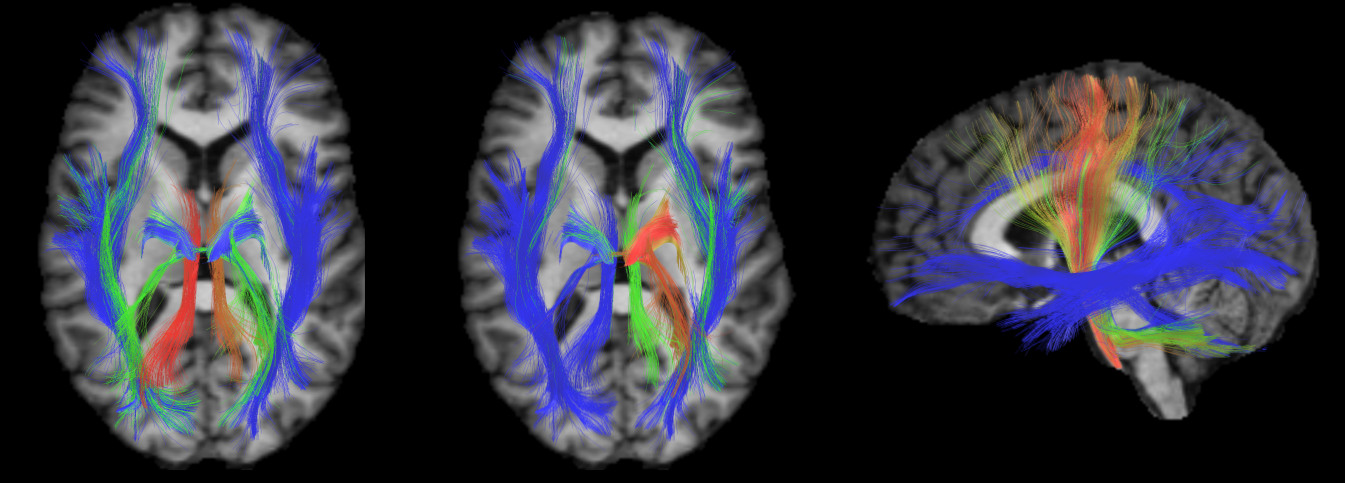

Refer to caption

Figure 2: Right sagittal (top) and inferior axial (bottom) views of the ground truth, and bundles obtained by KSC (Smax=3subscript𝑆max3S_{\mathrm{max}}=3) using the Haus, MCP and EP.

Figure 2 compares the ground truth clustering of the SCIL dataset with the outputs of KSC (Smaxsubscript𝑆maxS_{\mathrm{max}}=3) using the Haus, MCP and EP distances. Except for the superior cerebellar peduncle bundle (cyan and green colors in the ground truth), the bundles obtained by KSC+MCP and KSC+Haus are similar to those of the ground truth clustering. Also, we observe that the differences between KSC+MCP and KSC+Haus occur mostly in the right inferior fronto-occipital fasciculus and inferior longitudinal fasciculus bundles (yellow and purple colors in the ground truth). Possibly due to the large variance of endpoint distances in individual bundles, KSC+EP gives poor clustering results.